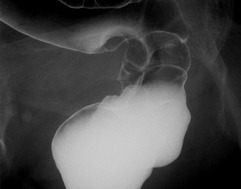

1:上部消化管造影検査

バリウムを飲んで、食道・胃・十二指腸をレントゲンで調べる検査です。これを病院で行うのが一般に直接撮影と呼ばれ、検診車で撮影するのは間接撮影ということになります。直接撮影の方が細かい診断が可能ですから、どちらをするかと聞かれれば、迷わず直接撮影をお勧めします。患者さんに必要とされるのは、バリウムを飲むことができること、ゲップを我慢できること、寝台の上で右向いたり左向いたりうつ伏せになったり体を自由に動かせること、です。この検査では、良性の潰瘍や癌の発見などが可能ですが、ある種の早期癌については残念ながら発見は困難です。また、胃炎の細かい程度を知るのも難しく、組織をとって検査したりすることもできません。ただし、胃の形や伸展具合を知る上では優れています。

←矢印部分に大きな隆起性病変があるため、胃の膨らみ方が悪くなっています。  進行胃癌。